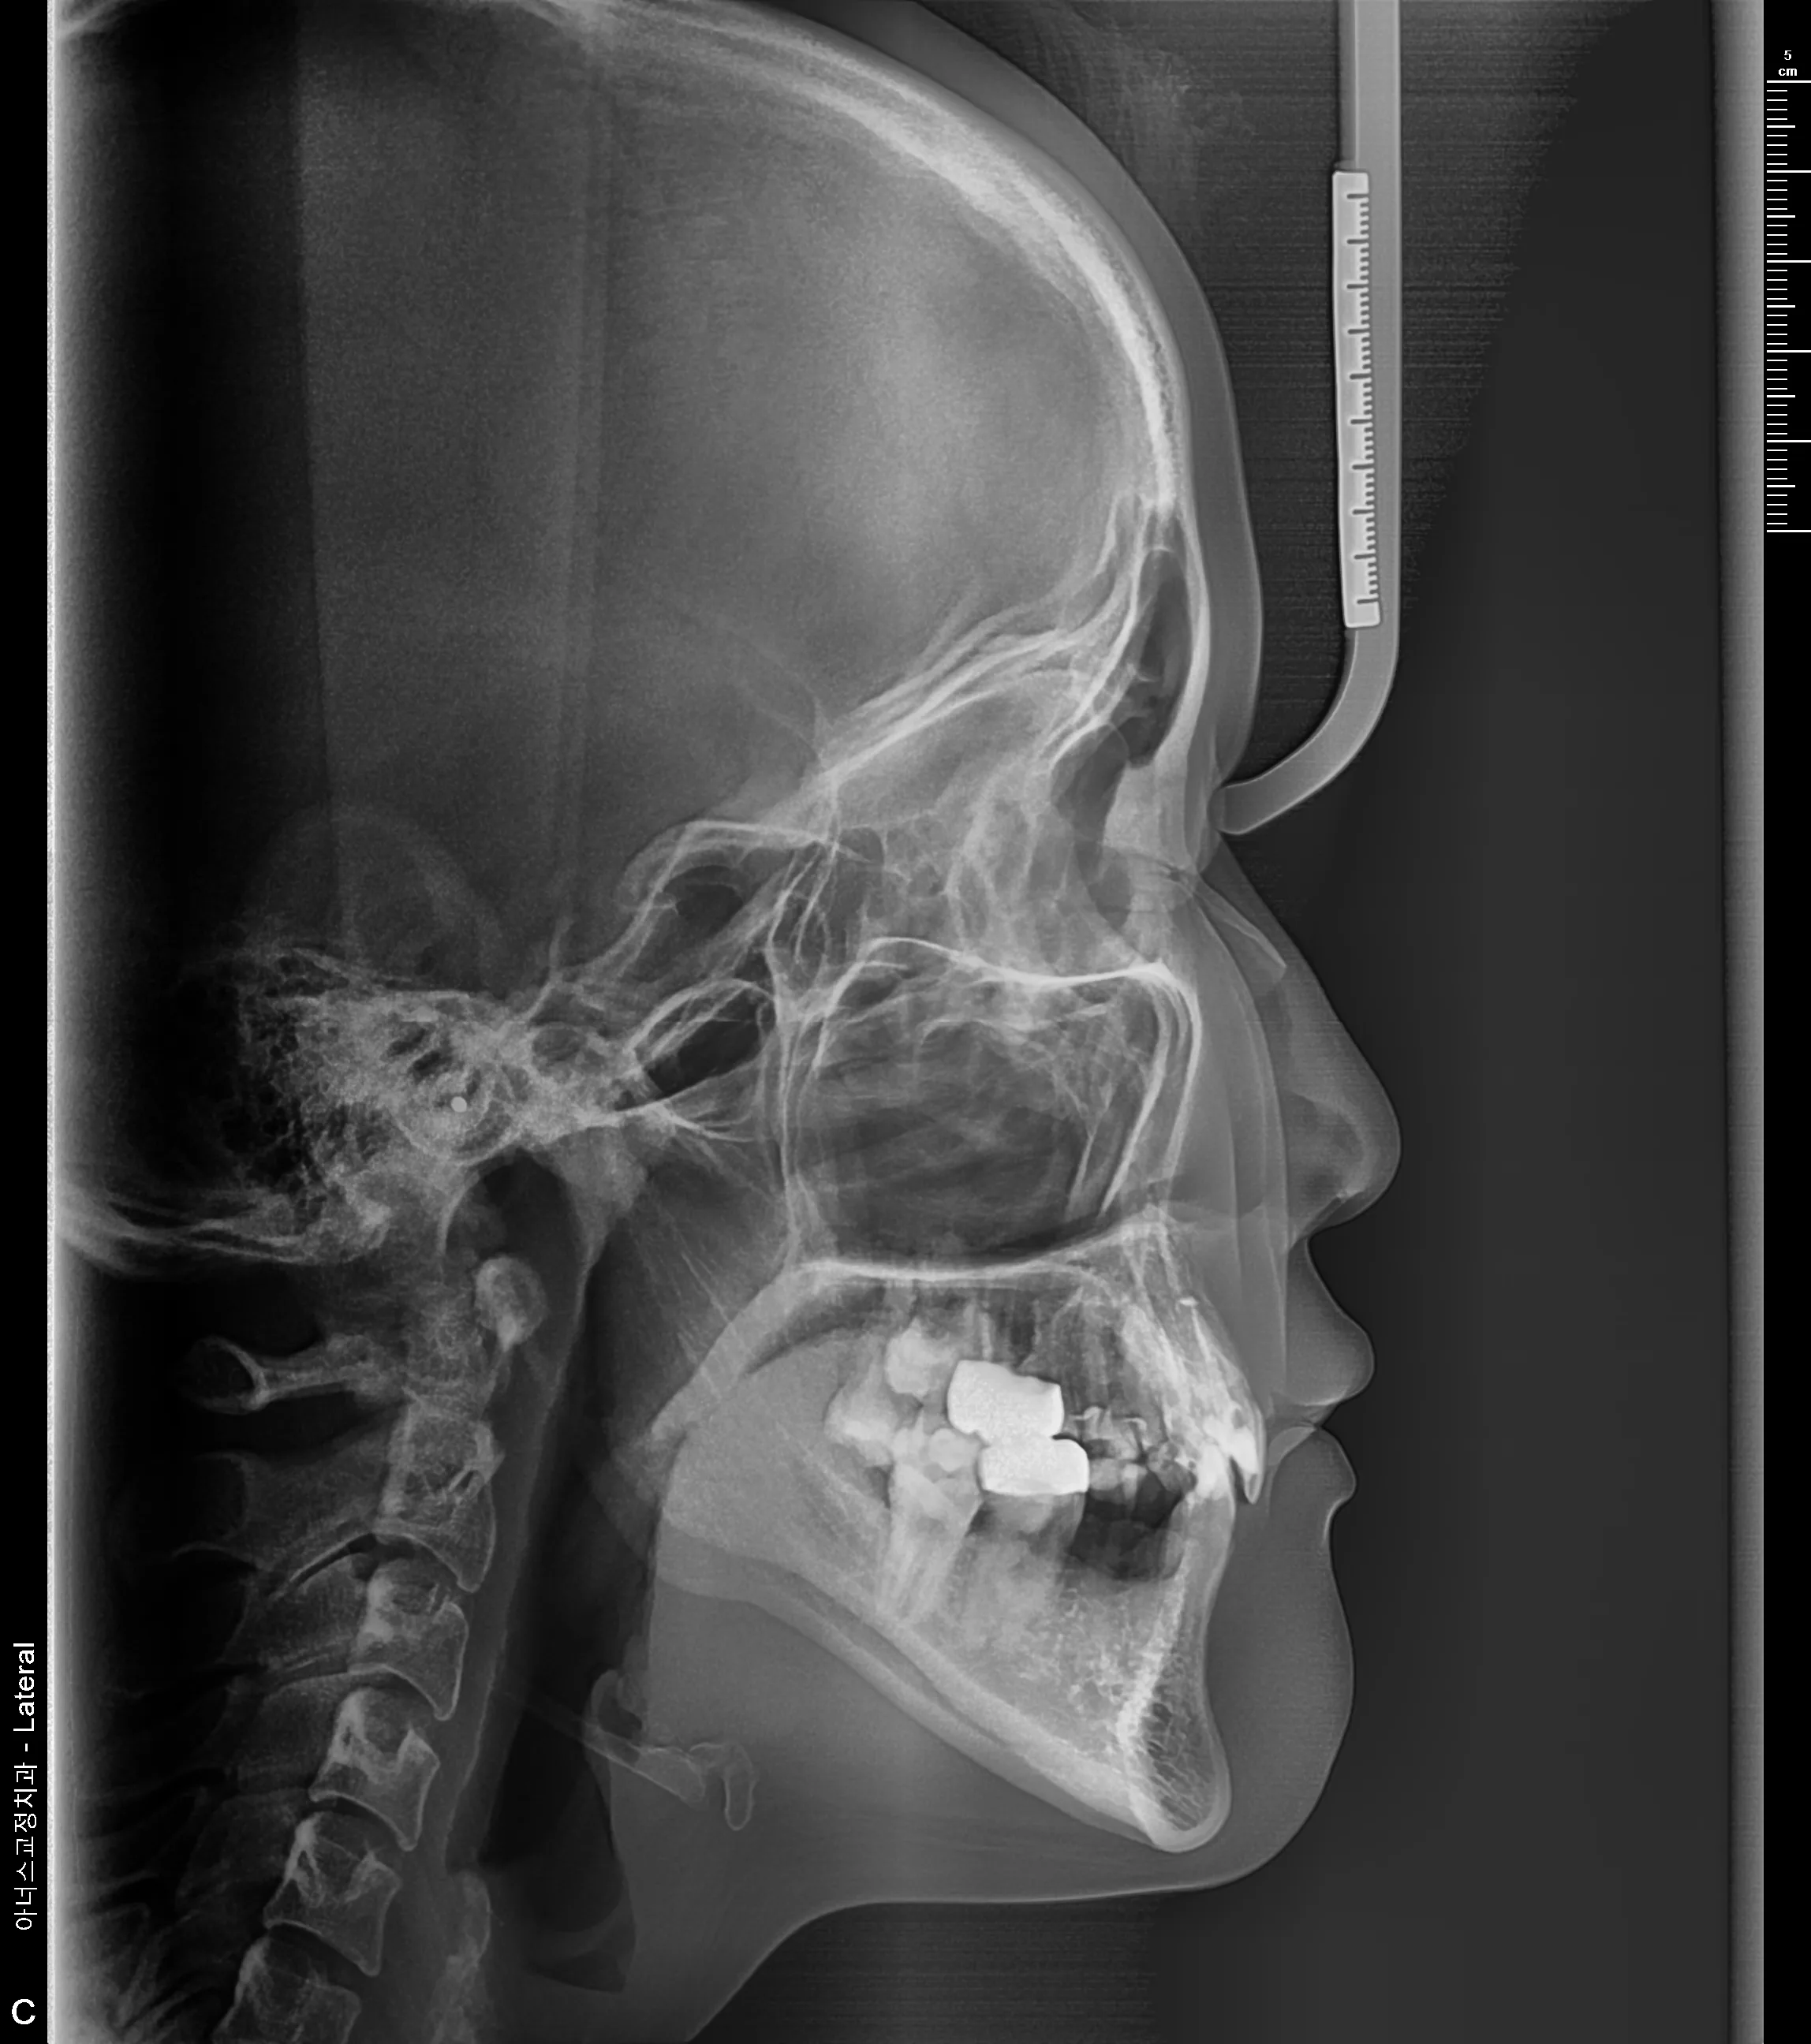

만 21세 환자로, 기존에 사고로 여러 치아를 다치고 상실한 상태로 매우 심한 교합무너짐이 있었습니다.

치료후 (After)

엑스레이